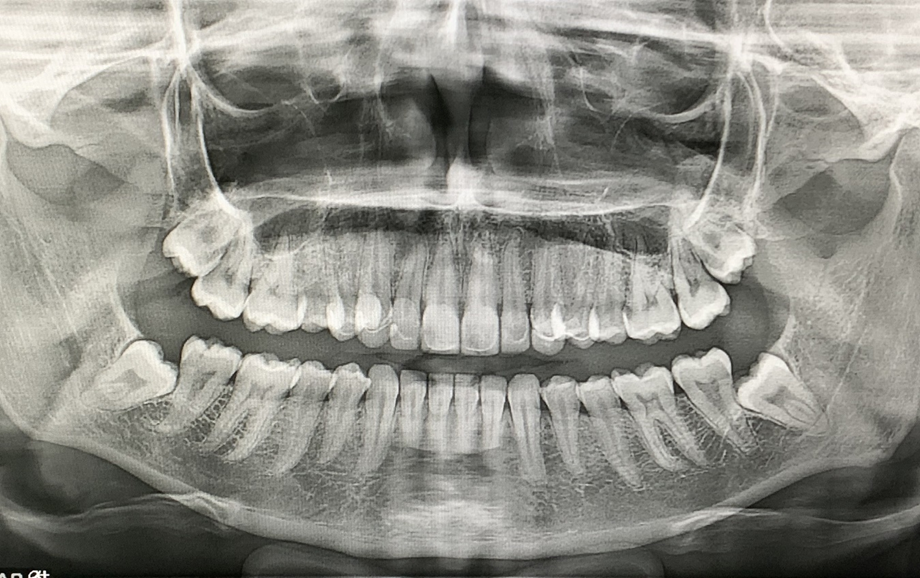

tomografía dental

Tomografía maxilar y mandibular con diagnóstico clínico y radiográfico

por sólo $1500.00 consulta incluida.

Se entrega en USB.